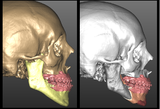

La programmazione dell’intervento chirurgico deve prevedere una stretta collaborazione tra chirurgo maxillo-facciale e ortodontista. La fase preoperatoria si conclude con la determinazione, mediante appositi software, del V.T.O. (Visual Treatment Objective) chirurgico in cui si stabiliscono le correzioni da eseguire sui singoli segmenti ossei. L’analisi cefalometrica, gli esami fotografici e radiografici (spesso Cone Beam TC), la valutazione dei modelli in gesso delle arcate dentarie consentono di delineare con precisione millimetrica gli spostamenti e/o le rotazioni dei vari segmenti scheletrici che saranno eseguiti in sede intraoperatoria.

Durante l’intervento si procede alla manipolazione degli elementi dello scheletro facciale per ottenere una corretta relazione anatomica e funzionale ossea e dentale.

Gli interventi di chirurgia ortognatica prevedono un accesso endorale che consente di eseguire le singole osteotomie precedentemente stabilite in fase di programmazione. Si distinguono: